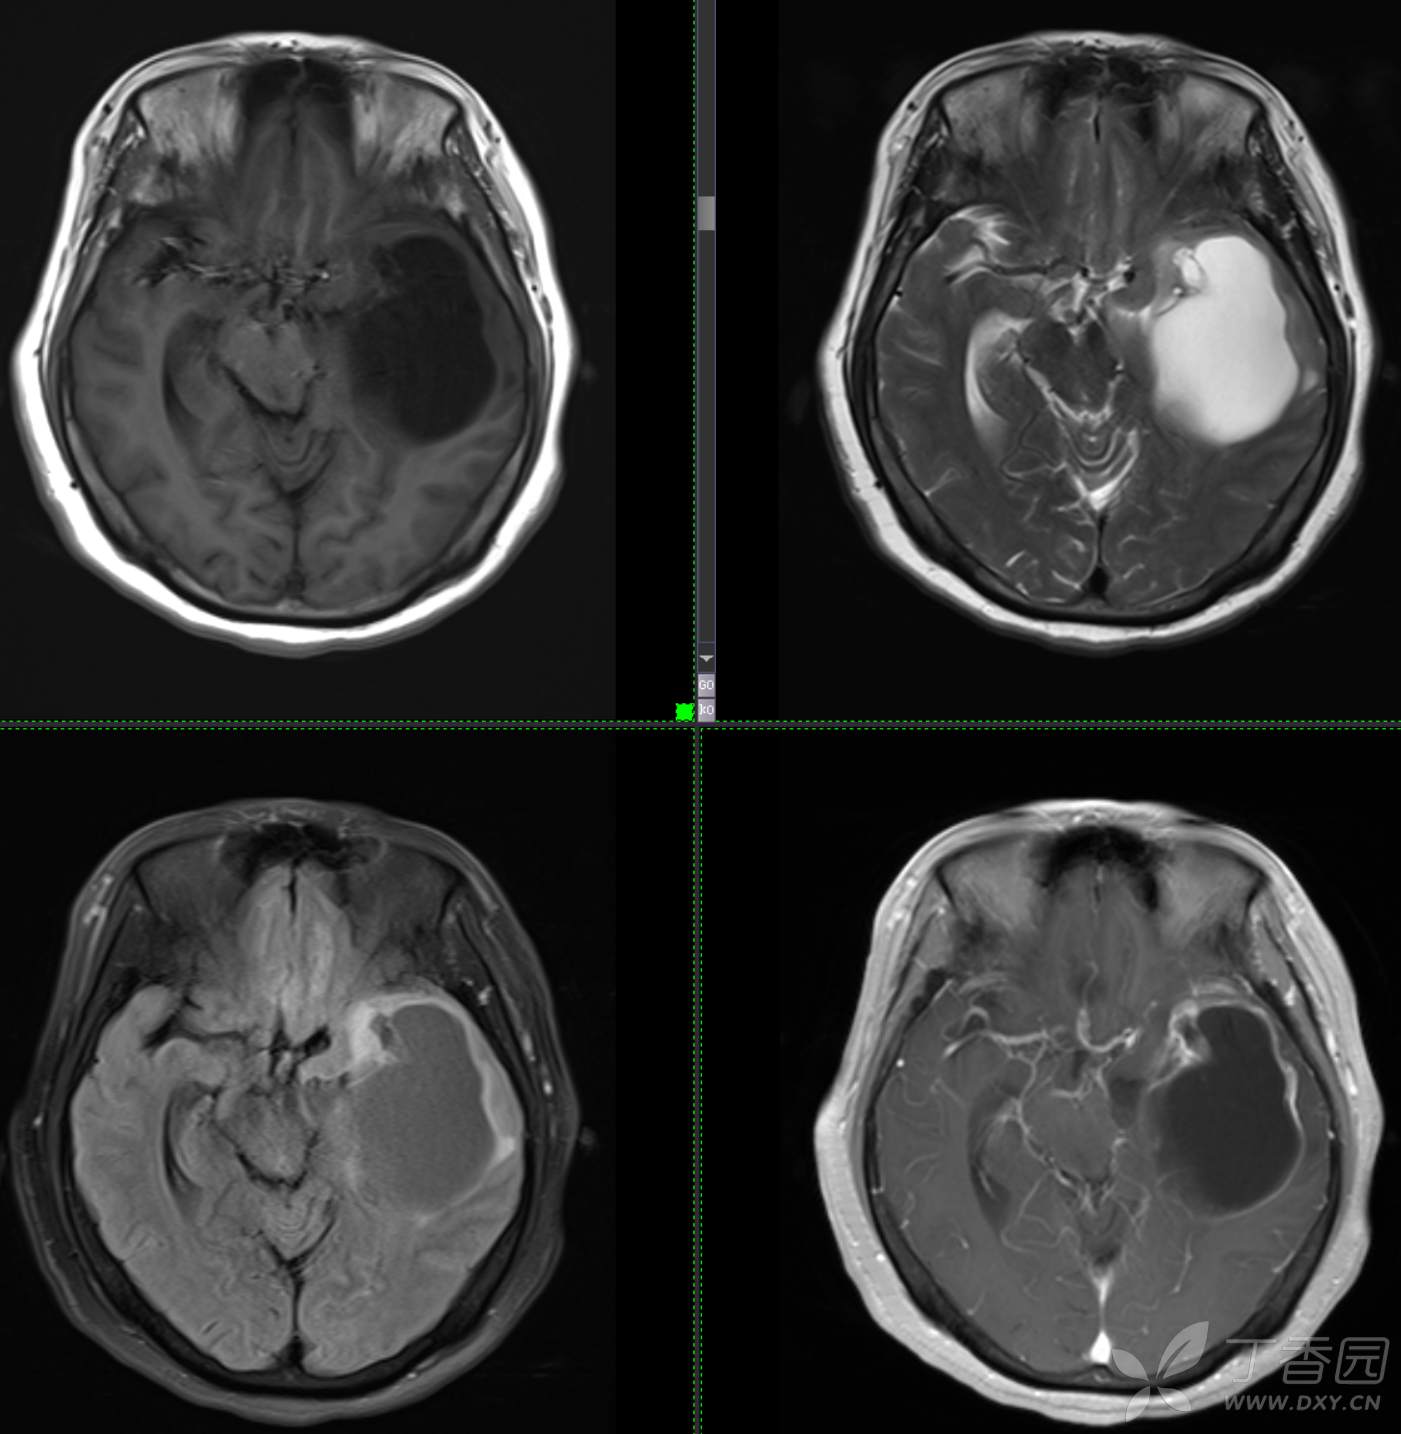

头颈组12:老年女性,原发?继发?

患者年龄:58岁

现病史: 【患者1月余前无明显诱因出现记忆力减退,易忘记事情,表现为忘记说过的话、易忘 事、理解力及计算力均尚可、阅读无受限、无性格脾气改变,无头痛头晕、无恶心呕吐、无视物模糊,无言语不利,无幻觉妄想,当时未重视未就诊。1月内记忆力减退进行性加重,对刚做过的事情即遗忘,计算力下降,日常生活尚能自理。遂至我院门诊就诊,查“颅脑CT平扫:左侧基底节-颞叶区低密度占位,建议进一步增强 MRI检查。

患者既往子宫内膜癌手术史;高血压病史3年